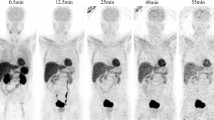

Volumes of Interest

Accumulation of [11C]preladenant in the stomach wall, liver, kidney, small intestine, and urinary bladder was clearly visual on the PET images (Figs. 1 and 2 and Supplementary Fig. 2). The highest tracer concentration was found in the duodenum and stomach wall, showing maximum SUVs of 28.4 ± 7.9 and 18.9 ± 3.1 (imaging data), respectively, at 90 min post injection. PET imaging and organ harvesting gave comparable SUVs, as is shown in Fig. 3. Figure 4 illustrates the dynamic distribution of [11C]preladenant in multiple rat organs derived from PET imaging and organ harvesting. The activity was corrected for decay to the time of injection. The highest total organ tracer uptake was found in the liver, with a peak of 39.2 ± 4.3 % injected activity at 8.5 min post injection for PET-imaging data, and 28.6 ± 9.5 % injected activity at 5 min post injection for ex vivo biodistribution data. The brain, kidneys, heart, lungs, spleen, and pancreas displayed rapid tracer clearance, with a peak uptake within 1 min. The small intestine, large intestine, stomach, and urinary bladder exhibited continuously increasing uptake for the total scan duration of 90 min.

The highest organ dose was received by the small intestine (imaging: 23.2 μSv/MBq, harvesting: 25.1 μSv/MBq), and followed by the liver (imaging: 16.8 μSv/MBq, harvesting: 15.1 μSv/MBq), stomach wall (imaging: 8.9 μSv/MBq, harvesting: 12.5 μSv/MBq), and the kidneys (imaging: 8.4 μSv/MBq, harvesting: 7.2 μSv/MBq) (Table 3). ED estimates were similar between PET-imaging and organ-harvesting methods, being 5.1 ± 0.3 μSv/MBq for PET-imaging, and 5.1 μSv/MBq for organ-harvesting, with a range between 4.4 and 5.8 μSv/MBq (ICRP 103). When the weighting factors from ICRP 60 were used in the calculation, the resulting EDs were 5.5 ± 0.4 μSv/MBq for PET-imaging, and 5.6 μSv/MBq for organ-harvesting. When the source organs listed in Table 2 were reduced to organs with uptake visually higher than the background on the PET image (stomach, liver, kidney, small intestine, urinary bladder, lungs (lungs were not visible on the PET image, however the activity concentration in lungs was 3.3 times higher than presented on the image. Therefore, lung was also included as a source organ); Figs. 1 and 2), the EDs based on RT values of lungs and visible source organs only were 4.7 ± 0.2 μSv/MBq for PET-imaging, and 4.6 μSv/MBq for organ-harvesting, based on ICRP 103, and was 5.1 μSv/MBq for both PET-imaging and organ-harvesting, based on ICRP 60.